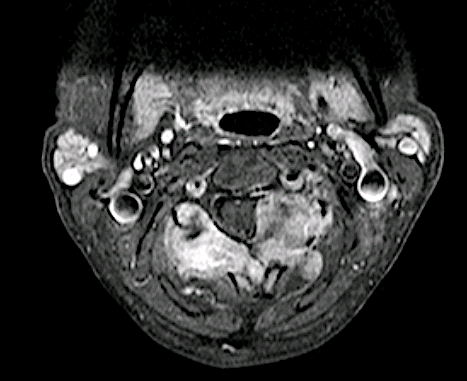

Paciente con metástasis de carcinoma gástrico GIST resistente a QT y RT, con progresión de enfermedad. La paciente refiere dolor local sin clínica de mielopatía previo a cirugía.

Tumoración arco posterior de C3 con invasión de canal vertebral, adherido a foramen vertebral izquierdo.

El caso presentaba interés quirúrgico porque el tumor presentaba límites imprecisos (extracompartimental), parecía estar en relación con arteria vertebral dominante y comprimía el saco dural. Se realizó un abordaje posterior para exéresis macroscópica completa. La arteria vertebral se disecó perfectamente al no estar englobada en la masa.